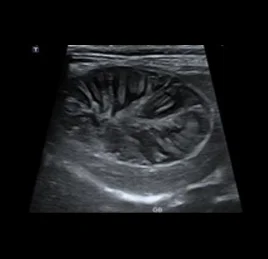

• 비장 종양

• 부신 종양

• 소장 종양